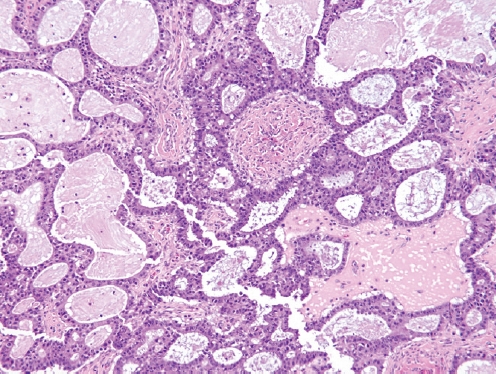

Pathology Outlines - Mucinous borderline tumor